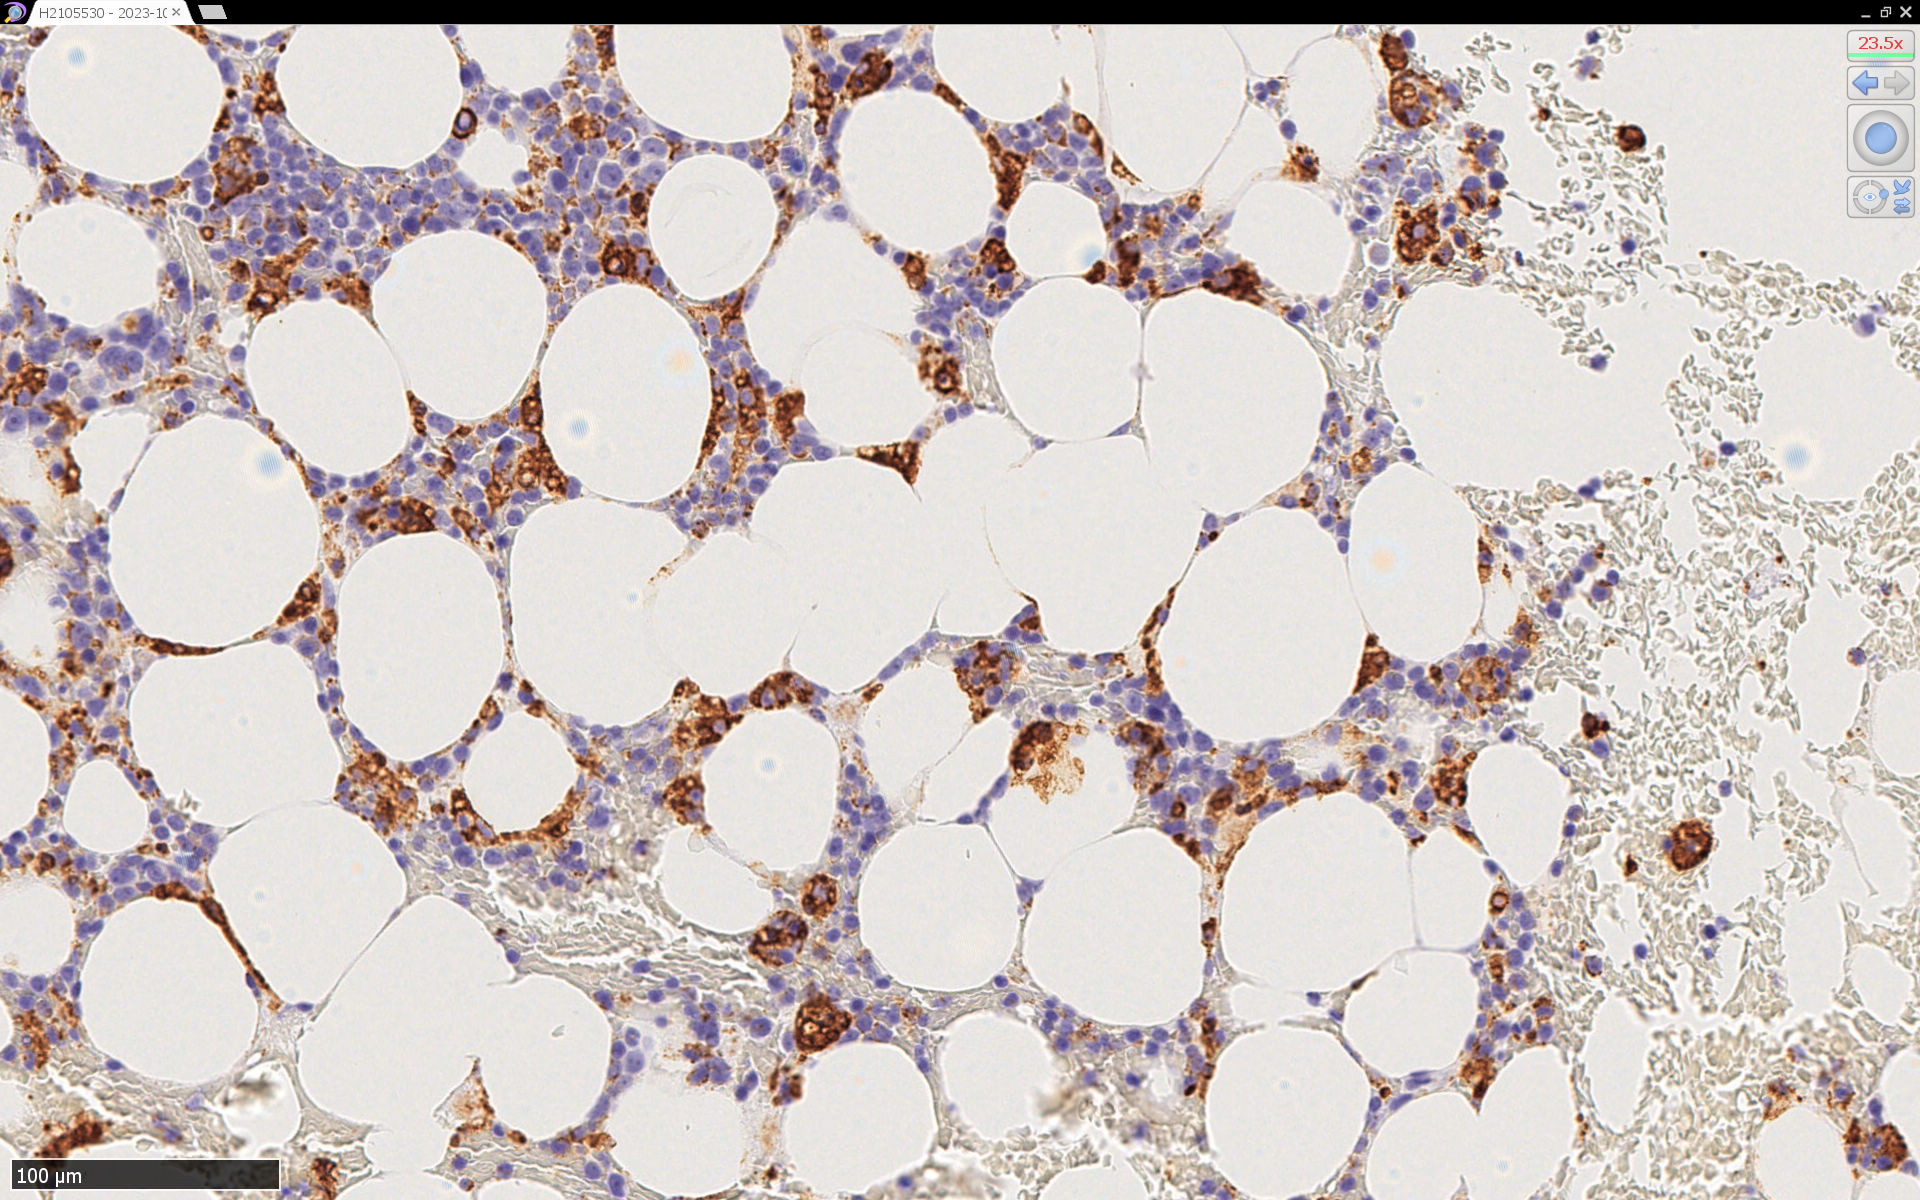

CD68(KP-1)

CD68(PG-M1)